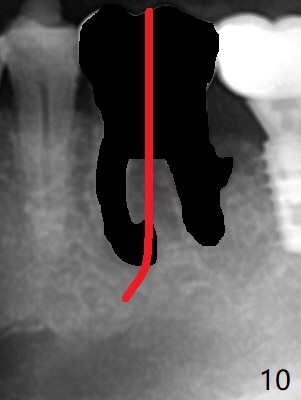

Venopuncture is conducted (Fig.1) for PRF and sticky bone (cortical chip and .5 cc ß-TCP). After use of proximators at #19, cowhorn forceps are applied, resulting in metal crown dislodgement. Since there is distal bone loss, distal socket sheath is contemplated. The tooth is sectioned. When an elevator is inserted between the roots, the distal root is loosened first. The 2 roots are removed, revealing a rounded end septum (Fig.2 S) and a larger distal socket. To avoid osteotomy deviation over the septum, a 12 mm bone trimmer is used, followed by point drill (Fig.3 *). But the lower half of the implant is deviated mesial (Fig.4) with decreased torque (~ 10 Ncm). To overcome this misfortune, the roots should not be removed until osteotomy is finished. Dual zones of bone graft is conducted. Sticky bone is placed until the plateau of the implant with a healing screw in place (Fig.4 * (bone zone)). After placement of a pair abutment, the same bone graft is packed until the margin of the abutment (Fig.5 * (soft tissue zone)). An immediate provisional is fabricated to close the socket with a piece of PRF as well. Fig.6-11 explains why the lower half of the implant deviates to the mesial socket, while Fig.12-16 illustrates how to prevent the deviation. After extraction of #19 (Fig.6,7), the crest of the septum is flattened (Fig.8 arrowhead) to prevent the initial deviation (Fig.9 red line). When a drill reaches a space (a socket, mesial in this case), the drill is deflected to the least resistant area (Fig.10 a bent red line), leading to the implant deviation apically (Fig.11 green). To prevent the apical deviation, therefore, the roots of the affected tooth is temporarily not removed (Fig.12). The osteotomy should not deviates with surgical guide because of similar density between the tooth and the bone (Fig.13). When the osteotomy is finished (Fig.14), the roots are extracted (Fig.15). The implant to be placed should not have deviation (Fig.16 green). The papillae are maintained by the immediate provisional 11 days postop (Fig.17). The incompletely seated abutment at #18 (Fig.5 <) is reseated completely 6 months postop (Fig.18). Crestal bone forms distal to #19 implant. There is no bone loss 4 months and 3 years 1 month post cementation at #19 and 18, respectively (Fig.19,20).